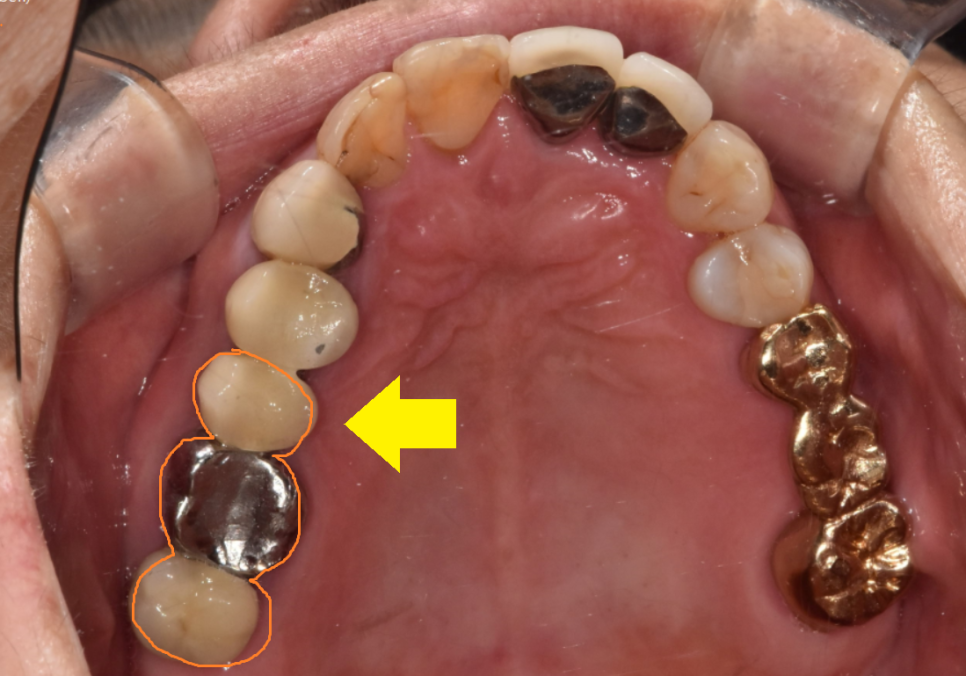

문제의 치아 입니다.

묶어있는 형태였는데요.

23.10.10

아직 반대편 치료가 다 끝나지 않았는데

기존 보철이 빠져버렸네요ㅠㅠ

한눈에 보기에도 상태가 좋지 않죠~?